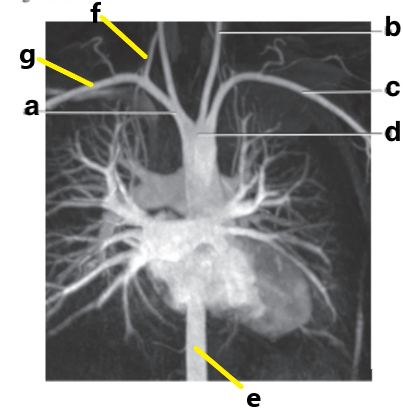

What is letter a ?

Brachiocephalic trunk

Which letter is the Descending aorta ?

f

Which letter is the ascending aorta ?

Ascending aorta

Which letter is the right subclavian artery ?

g

c

Which letter is the Left common carotid ?

b